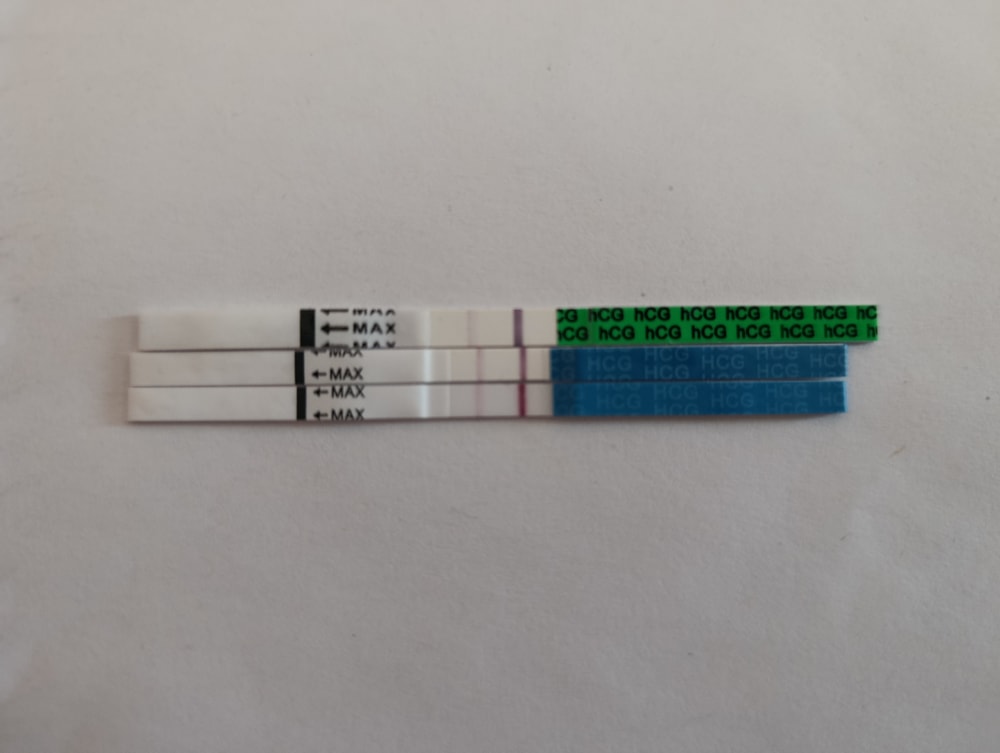

Обследования, узи, анализыТесты показывают "сомнительно" Положительную беременность

Ну тут вообще не сомнительно, у вас четкие полоски , сдайте ХГЧ и отслеживайте рост, когда будет больше 1000 или те на узи)

Ну какие же они сомнительные....они прям положительные! Слышала от мамочек много таких историй, как их киста в 1 класс пошла,в армию и тд